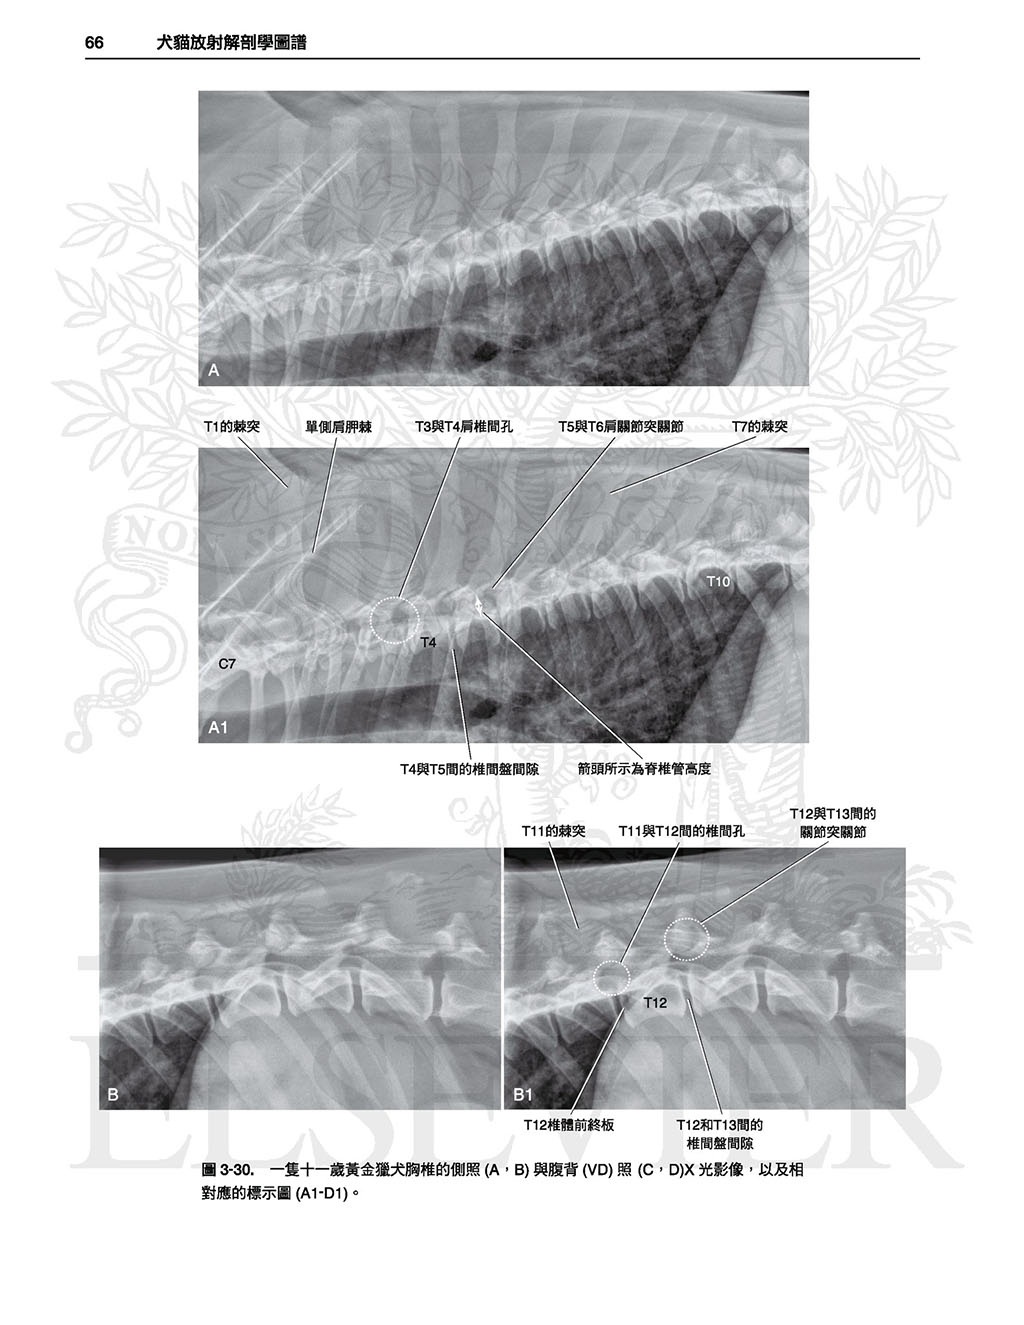

3脊椎, 48